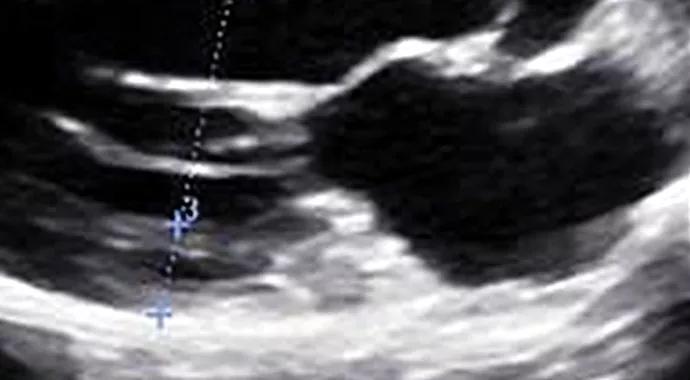

He comes to Cleveland Clinic’s Sports Cardiology Center for a second opinion. The septal wall measurements are confirmed on echocardiogram (left image below). While up to 18 percent of African-American athletes have septal wall thickness greater than 12 mm, this finding is unusual in a white athlete. However, diastolic function and longitudinal strain are normal (see systolic strain profile at bottom of post).

Series of three echo and MRI images from page 3 of Summer Cardiac Consult

He performs well on a metabolic stress test (VO2 max is 64.3 mL/kg/min), and MRI reveals no scar and a normal mitral valve apparatus. Close evaluation of the MRI reveals that the septal measurement from long-axis view was overestimated due to a tangential cut through the septum and inclusion of right ventricular trabeculation (middle image above). The true septal measurement is determined to be 11 mm (right image above). The collective findings are believed to be related to “athlete’s heart,” and the patient is allowed to return to play.